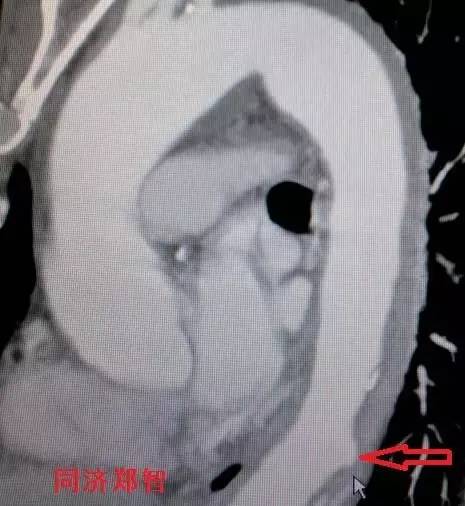

三维重建显示主动脉弓穿透性溃疡,与图11为同一病人(图12)。

图12